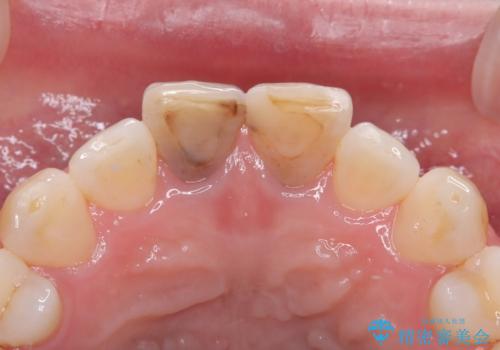

セラミッククラウンで前歯の変色を改善

- 前歯の変色が気になるというご相談をいただき、セラミッククラウンによる治療を行いました。

セラミッククラウンによって前歯の変色が改善され、また歯の形も希望の形態へ修正しました。